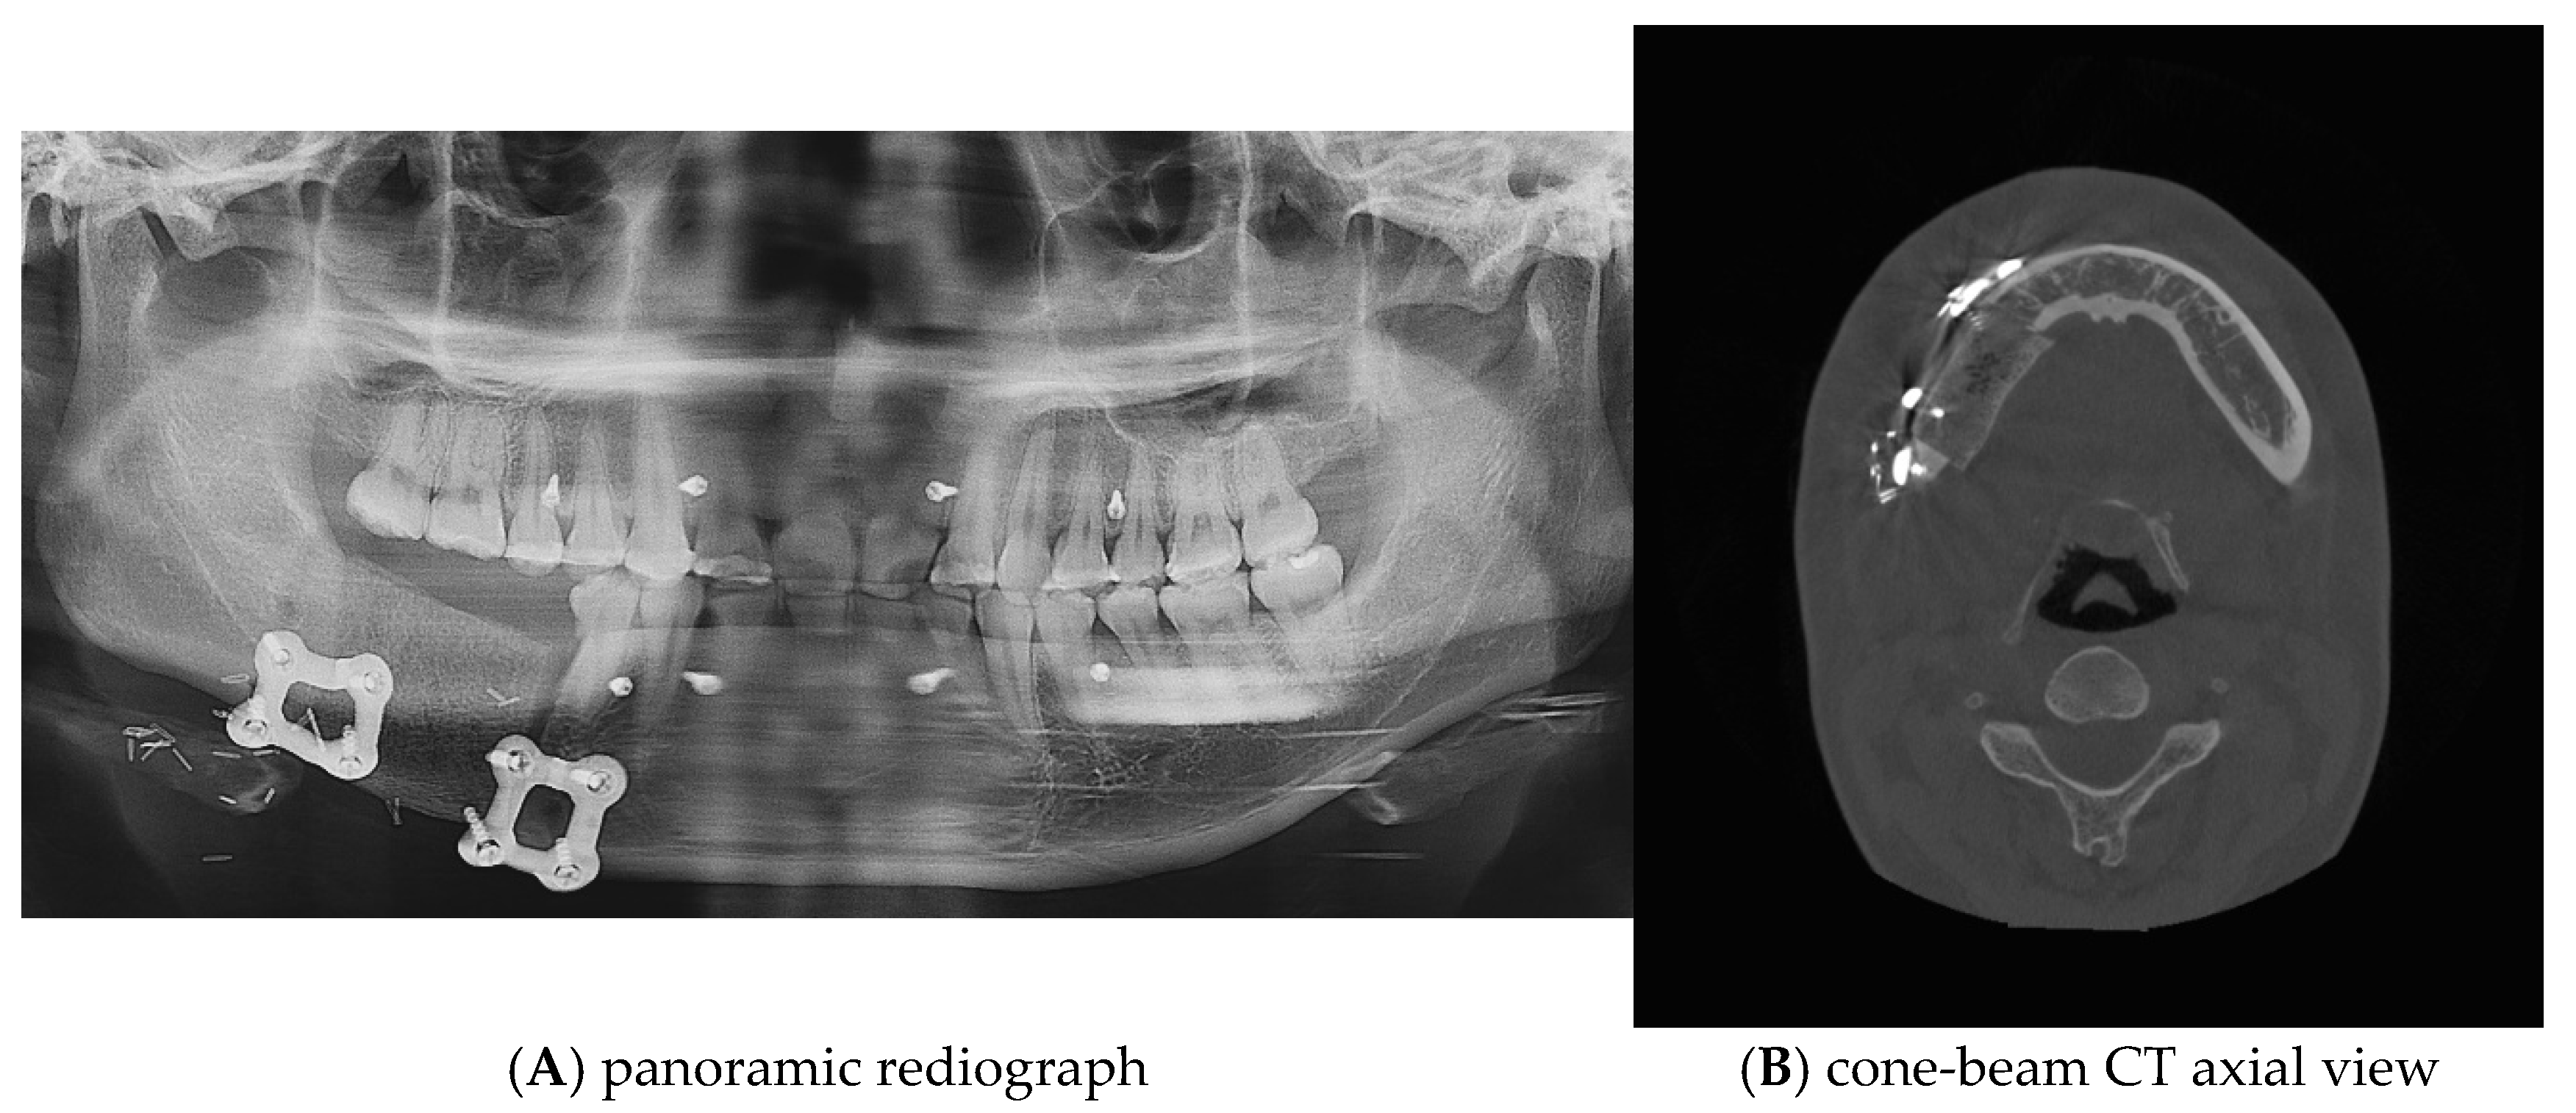

Postoperative panoramic radiographs and CBCT imaging were obtained to evaluate the error compared to the preoperative plan. (Figure 11) The evaluation was performed using Materialize 3-matic software. After aligning the preoperative plan STL model and the postoperative STL model, the average value was obtained through analysis of the difference between the two models. the average discrepancy was 0.79 mm. During the 6-month follow-up period after surgery, occlusion and mouth opening were stable.

Figure 11.

Postoperative panoramic radiograph and cone-beam CT. A high level of precision was achieved in the reconstruction.

One of the primary benefits observed in this case was the high level of precision achieved in the reconstruction. Postoperative panoramic radiographs and cone-beam CT scans showed that the actual reconstruction closely matched the virtual surgical plan (Figure 12A,C). When comparing the overall preoperative and postoperative results, the average discrepancy was 0.90 mm. This level of accuracy is consistent with findings in the literature, where studies have reported average differences between virtual plans and postoperative results ranging from 0.9 mm to 3.0 mm [9,19,20,21,22,23,24,25,26,27].

Figure 12.

(A–C): Comparison of preoperative and postoperative flap designs. The rulers on the left and bottom indicate length (cm).